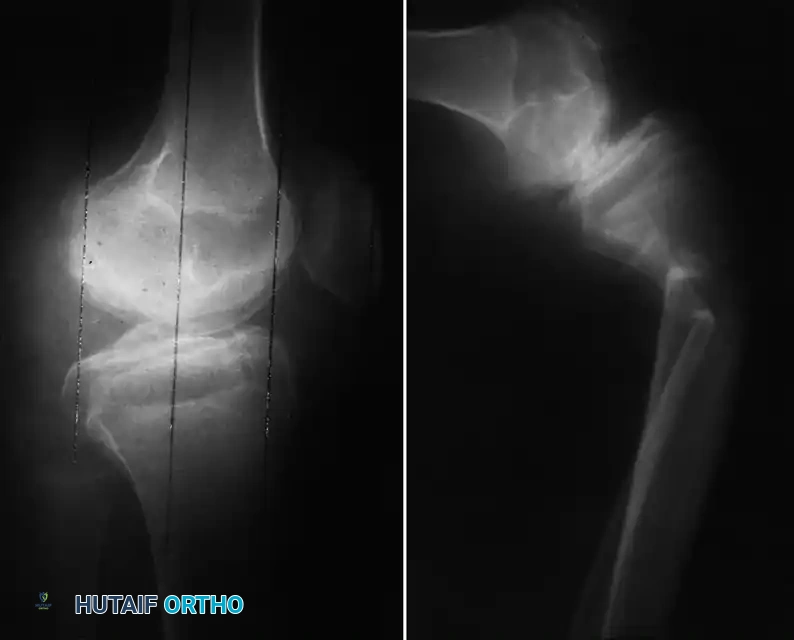

Image

Fig. 29-35: Damaged knee joint with hemophilia (factor VIII deficiency). Note the marked destruction and erosion of the articular surface of the femoral condyle, gross erosion of the tibial plateaus, and complete destruction of the menisci by invasive hypertrophic synovium.

Fig. 29-36: Late complications of hemophilic arthropathy. Severe disuse osteopenia significantly increases the risk of periprosthetic fractures and iatrogenic fractures during postoperative manipulation or physical therapy.

Intraoperative fractures during implant seating, or postoperative fractures during physical therapy manipulation, are significant risks. Furthermore, the historical use of pooled plasma products left many older hemophilic patients HIV or HCV positive. This immunocompromised state drastically increases the risk of periprosthetic joint infection (PJI), requiring meticulous surgical technique and prolonged postoperative surveillance.